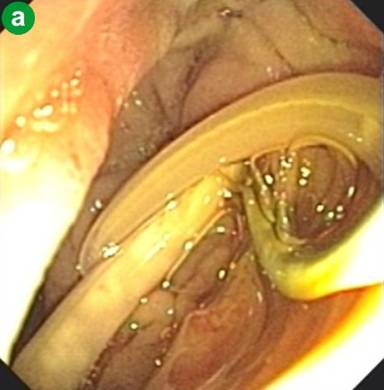

A 33-year-old healthy woman was born and lives in Bangkok which is the largest urban area of Thailand. She works as a secretary of a private company. She loves eating fresh vegetables. She had the history of intermittent epigastric pain for two months and presented with severe abdominal pain radiating to her back with nausea and vomiting for one day. Physical examination revealed febrile (37.5°C), no jaundice, marked tenderness at epigastrium and decreased bowel sound. Laboratory testing results showed leukocytosis of 11.7 x103/µL (reference range: 4.0-11.0 x103/µL) with 72% granulocytes (reference range: 40-74%) and 3% eosinophil (reference range: 0-7%), AST 105 U/L (reference range: 0-40 U/L), ALT 157 U/L (reference range: 0-40 U/L), alkaline phosphatase 229 U/L (reference range: 32-92 U/L), total bilirubin 1.4 mg/dL (reference range: 0.3-1.2 mg/dL), direct bilirubin 1.0 mg/dL (reference range: 0-0.5 mg/dL) and serum amylase 2,036 U/L (reference range: 0-220 U/L). Stool testing for parasites and ova were negative for three days. Abdominal computed tomography (CT scan) showed dilated common bile duct (0.8 cm in diameter) without filling defects and no gallstone. No evidence of acute pancreatitis was found from this study. She was initially diagnosed with acute mild gallstone pancreatitis with suspected retained common bile duct stone by over all clinical manifestations. Endoscopic retrograde cholangiography was performed and swollen ampulla with purulent bile were noted (Figure 1). Cholangiogram showed dilated common bile duct of 1.2 cm and there was a cylindrical filling defect about 6-7 cm in length inside the common bile duct (Figure 2). After endoscopic sphincterotomy, the parasite popped out and was extracted, using an extraction balloon catheter, then removed with a snare. The cholangiogram after removing this parasite showed markedly decreased in size of common bile duct without residual filling defect. The parasite in duodenum was shown in Figure 3. It was identified as a 22 cm long adult form of Ascaris lumbricoides (Figure 4).

Figure 3. The endoscopy revealed a roundworm extracted from ampulla of Vater and floating in the duodenum. |